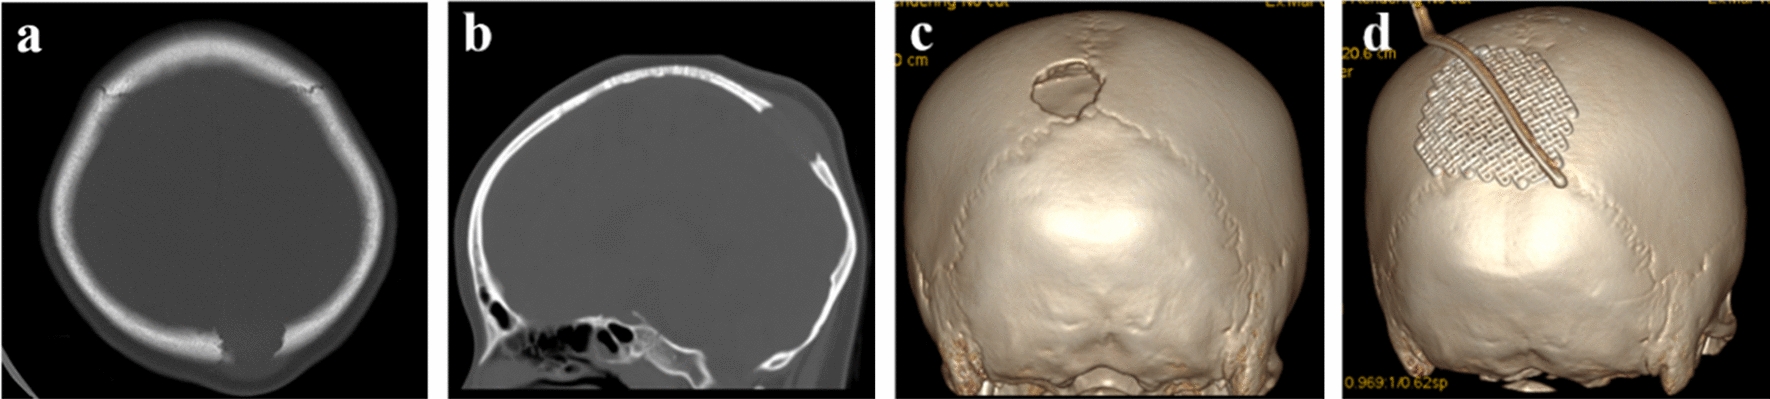

All 16 cases in this group underwent total lesion resection, of which 2 cases were found to have dural invasion, and the remaining 7 cases underwent biopsy of the lesions. During the surgery, the diseased tissue was removed and the surrounding abnormal bone tissue was bitten. Among them, individual lesions with a diameter exceeding 3 cm were repaired with titanium mesh for skull repair (Fig. 1). The intraoperative lesion is a grayish yellow and reddish brown granulation like tissue beneath the periosteum, with a brittle texture, rich blood supply, and no obvious capsule. The edge of the skull defect is osteoporotic, and granulation like tissue can be seen embedded in the plate barrier. Under the microscope, diffuse proliferation of Langerhans cells can be observed, with infiltration of eosinophils, neutrophils, lymphocytes, and multinucleated giant cells. Immunohistochemistry confirmed its pathological diagnosis.

Fig. 1.

Nine years and 4 months old girl, hospitalized due to the discovery of a subcutaneous mass on the left top for 1 month. a–c The skull bone defect and a subcutaneous mass on the left top. d. Titanium plate is trimmed and the skull defect is repaired